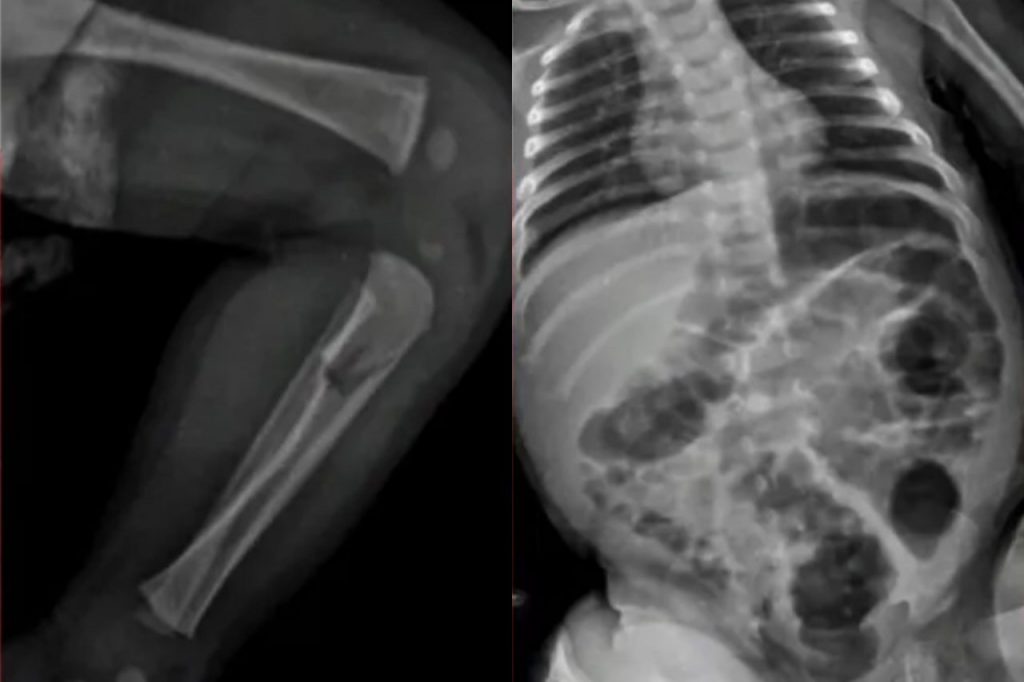

Os profissionais de saúde submeterem o bebê a exames de raio-x e descobriram que o menino sofreu lesões ósseas em uma das tíbias, em um antebraço e também nas costelas. Além disso, havia hematomas e escoriações pelo corpo.

Conforme o laudo médico, o bebê correu risco de morrer por conta dos ferimentos.